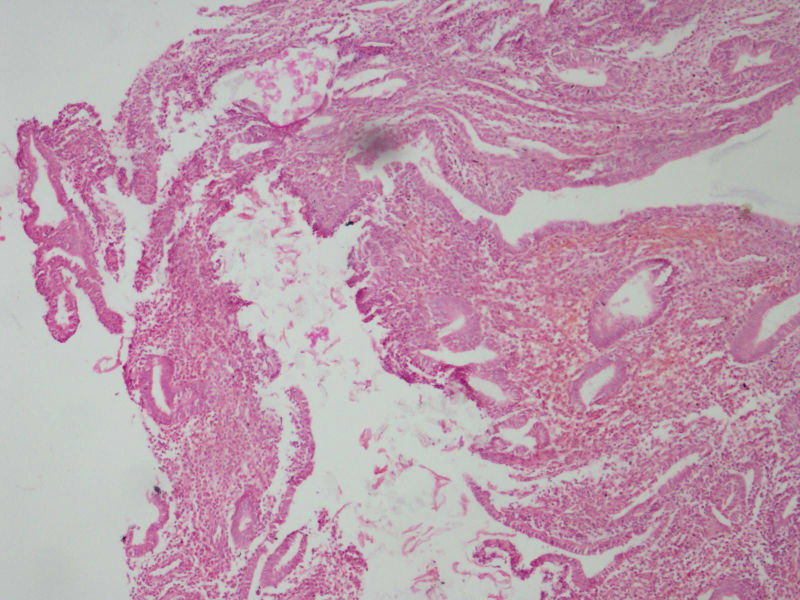

宫内膜

27结婚2年未避孕未怀孕停经4

染色偏红,感觉还是增值期子宫内膜。

增殖期宫内膜慢性炎症

增生期子宫内膜